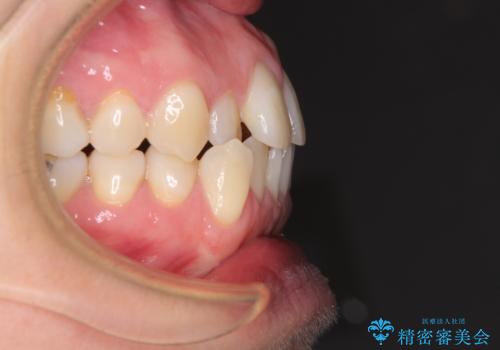

受け口傾向の歯並びをインビザラインで改善

- 受け口傾向でクロスバイトの前歯を治したいとのことで来院された患者様です。

下顎骨が若干左側に変位していたため、右側にアンカースクリューを使用し、積極的に移動させながらインビザラインにて矯正治療を行うこととしました。

インビザラインによる矯正治療は、受け口傾向の治療に非常に適した方法であり、事前にシミュレーションに沿って治療を進めることできます。

今回の治療では骨格的な偏位があったためアンカースクリューを使用し、より確率の高い治療を行うことができました。